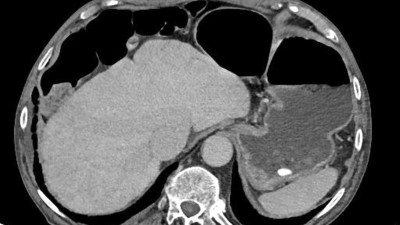

Aktuelle Bedeutung der Radiotherapie bei Plasmozytom und multiplem Myelom

Die Mehrzahl der Personen mit multiplem Myelom benötigt während ihres Krankheitsverlaufs eine lokale Therapie. Diese kann aufgrund von Schmerzen, (drohender) Instabilität oder neurologischer Symptomatik notwendig sein. Dabei kommen insbesondere eine Radiotherapie, operative Eingriffe oder eine Kombination der beiden Methoden zum Einsatz.

Chilaiditi-Syndrom in einer CT-Aufnahme/© Peters F & Ritz J-P/ all rights reserved Springer Medizin Verlag GmbH, Initial potenziell instabile Läsion von BWK 10 bei Multiplem Myelom/© Kaufmann, J., Schmidberger, H. / all rights reserved Springer Medizin Verlag GmbH, Springer Medizin Podcast - Endometriose/© (M) Willer D. et al. / all rights reserved Springer Medizin Verlag GmbH Logo: Springer Medizin Verlag GmbH, Zentrale Lungenembolie/© Springer Verlag Berlin Heidelberg 2015, Volumetrie des Bulbus olfactorius/© Keweloh S.. et al. doi.org/10.1007/s00106-025-01650-z unter CC-BY 4.0, Gebrochener Fuß im Gips/© Aleksandr Kirillov / stock.adobe.com (Symbolbild mit Fotomodell), CT-Pulmonalisangiographie/© Das M et al. doi.org/10.1007/s00117-016-0100-3 unter CC-BY 4.0, Kanüle für Katheterbehandlung/© romaset / stock.adobe.com, Komplexe, offene Fraktur des Ellenbogens vom Grad 2/© Springer Medizin Verlag GmbH, Mann erhält einen CT-Scan /© Mark Kostich / stock.adobe.com (Symbolbild mit Fotomodell), Verschlussazoospermie bei unilateraler zystischer Alteration der Samenblase und kontralateraler Samenblasenagenesie/© Wittler C et al, Indikationen zur konventionellen Bildgebung am Ellenbogen/© Rentschler V et al. / all rights reserved Springer Medizin Verlag GmbH, Person schenkt Bier in Kolben/© Parilov / Stock.adobe.com (Symbolbild mit Fotomodell), Neoadjuvanten Strahlentherapie bei Liposarkom/© Podleska, L.E. et al. / all rights reserved Springer Medizin Verlag GmbH, Frau erhält eine Strahlentherapie/© Mark Kostich / stock.adobe.com (Symbolbild mit Fotomodell), Schaumiges Bronchialsekret bei akutem Lungenödem/© Eichner M. doi.org/10.1007/s00063-025-01258-9 unter CC-BY 4.0, Bildgebung bei akuter Organblutung/© Nadjiri J / all rights reserved Springer Medizin Verlag GmbH, Bildgebung bei Beckenfraktur mit Blutung der A. iliaca interna/© Fink CB et al. / all rights reserved Springer Medizin Verlag GmbH, Traumatische Aortenverletzung/© Maier J et al. / all rights reserved Springer Medizin Verlag GmbH, Oberbauchsonoraphie/© C. Raschka, Muzinöses Prostatakarzinom/© Garzaro JRR et al. / all rights reserved Springer Medizin Verlag GmbH, Intraspinales thorakales Lipom/© Andreas Frank / all rights reserved Springer Medizin Verlag GmbH, Frau bei Strahlentherapie/© (M) Mark Kostich / Stock.adobe.com (Symbolbild mit Fotomodellen), Search Icon, Frau hält sich eine Brustseite nach Mastektomie/© chotiga / Stock.adobe.com (Symbolbild mit Fotomodell), Radiologin richtet Mammographiescreening ein/© LIGHTFIELD STUDIOS / stock.adobe.com (Symbolbild mit Fotomodellen)